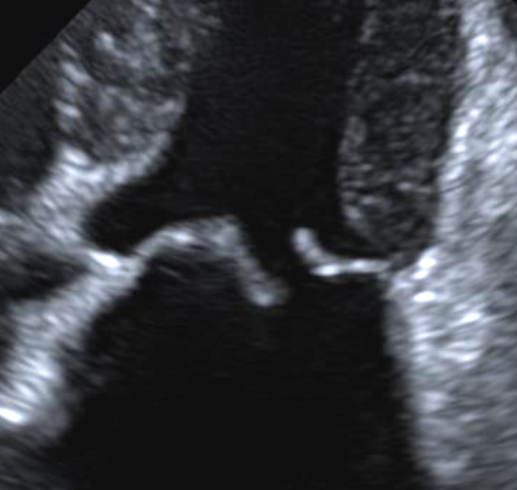

영상학적 소견 차이 : 심초음파(Echo) 상 건삭 파열의 전형적인 징후는 판막첨판의 이완 및 탈출(flail leaflet)입니다.

이는 승모판 첨단부가 수축기에 좌심방 쪽으로 젖혀지는 모습으로 확인되며, 건삭 파열의 확진 소견으로 간주됩니다.

이러한 flail leaflet 자체는 급성/만성 여부와 무관하게 건삭이 완전히 파열되면 나타나는 공통 소견입니다.

다만 급성 파열의 경우에는 새롭게 발생한 flail leaflet과 함께 즉각적인 중증 역류 제트가 보이고 좌심방 내 심한 난류가 관찰되며, 좌심방 크기에 비해 역류 정도가 과도한 모습을 보입니다.

반면 만성적 파열의 경우 이미 과거에 파열된 첨판의 flail이 관찰되더라도, 환자는 그동안 좌심방과 좌심실의 리모델링이 진행되어 심장이 크게 확장된 상태인 경우가 많습니다.